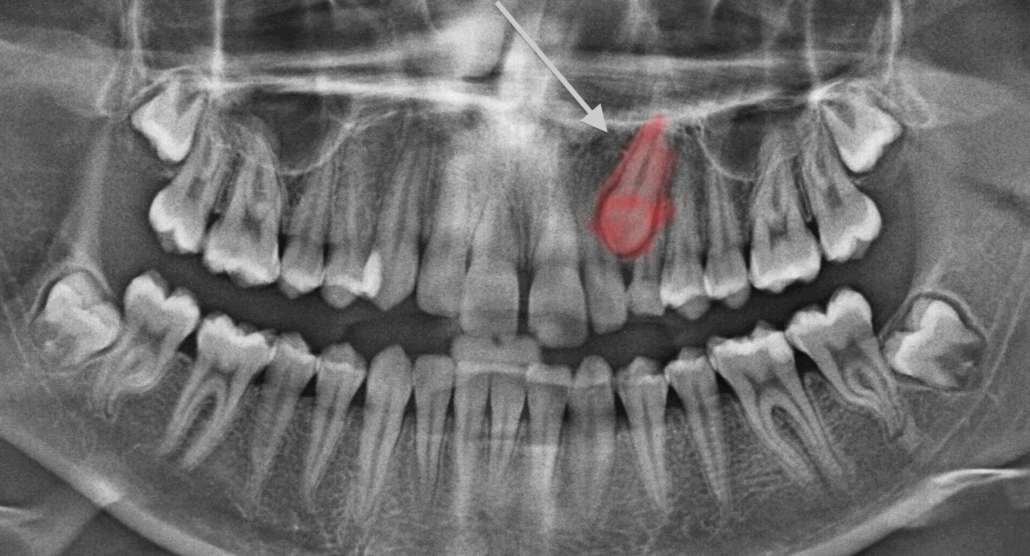

Une canine permanente (souvent supérieure) n’a pas fait son éruption normale.

Elle reste enfouie dans l’os ou sous la gencive, parfois mal orientée ou bloquée par d’autres dents.

Cela peut entraîner des complications : déplacement des autres dents, kyste, résorption radiculaire des dents voisines, asymétrie esthétique, etc.

Examen clinique + radiographie panoramique + scanner 3D si nécessaire.